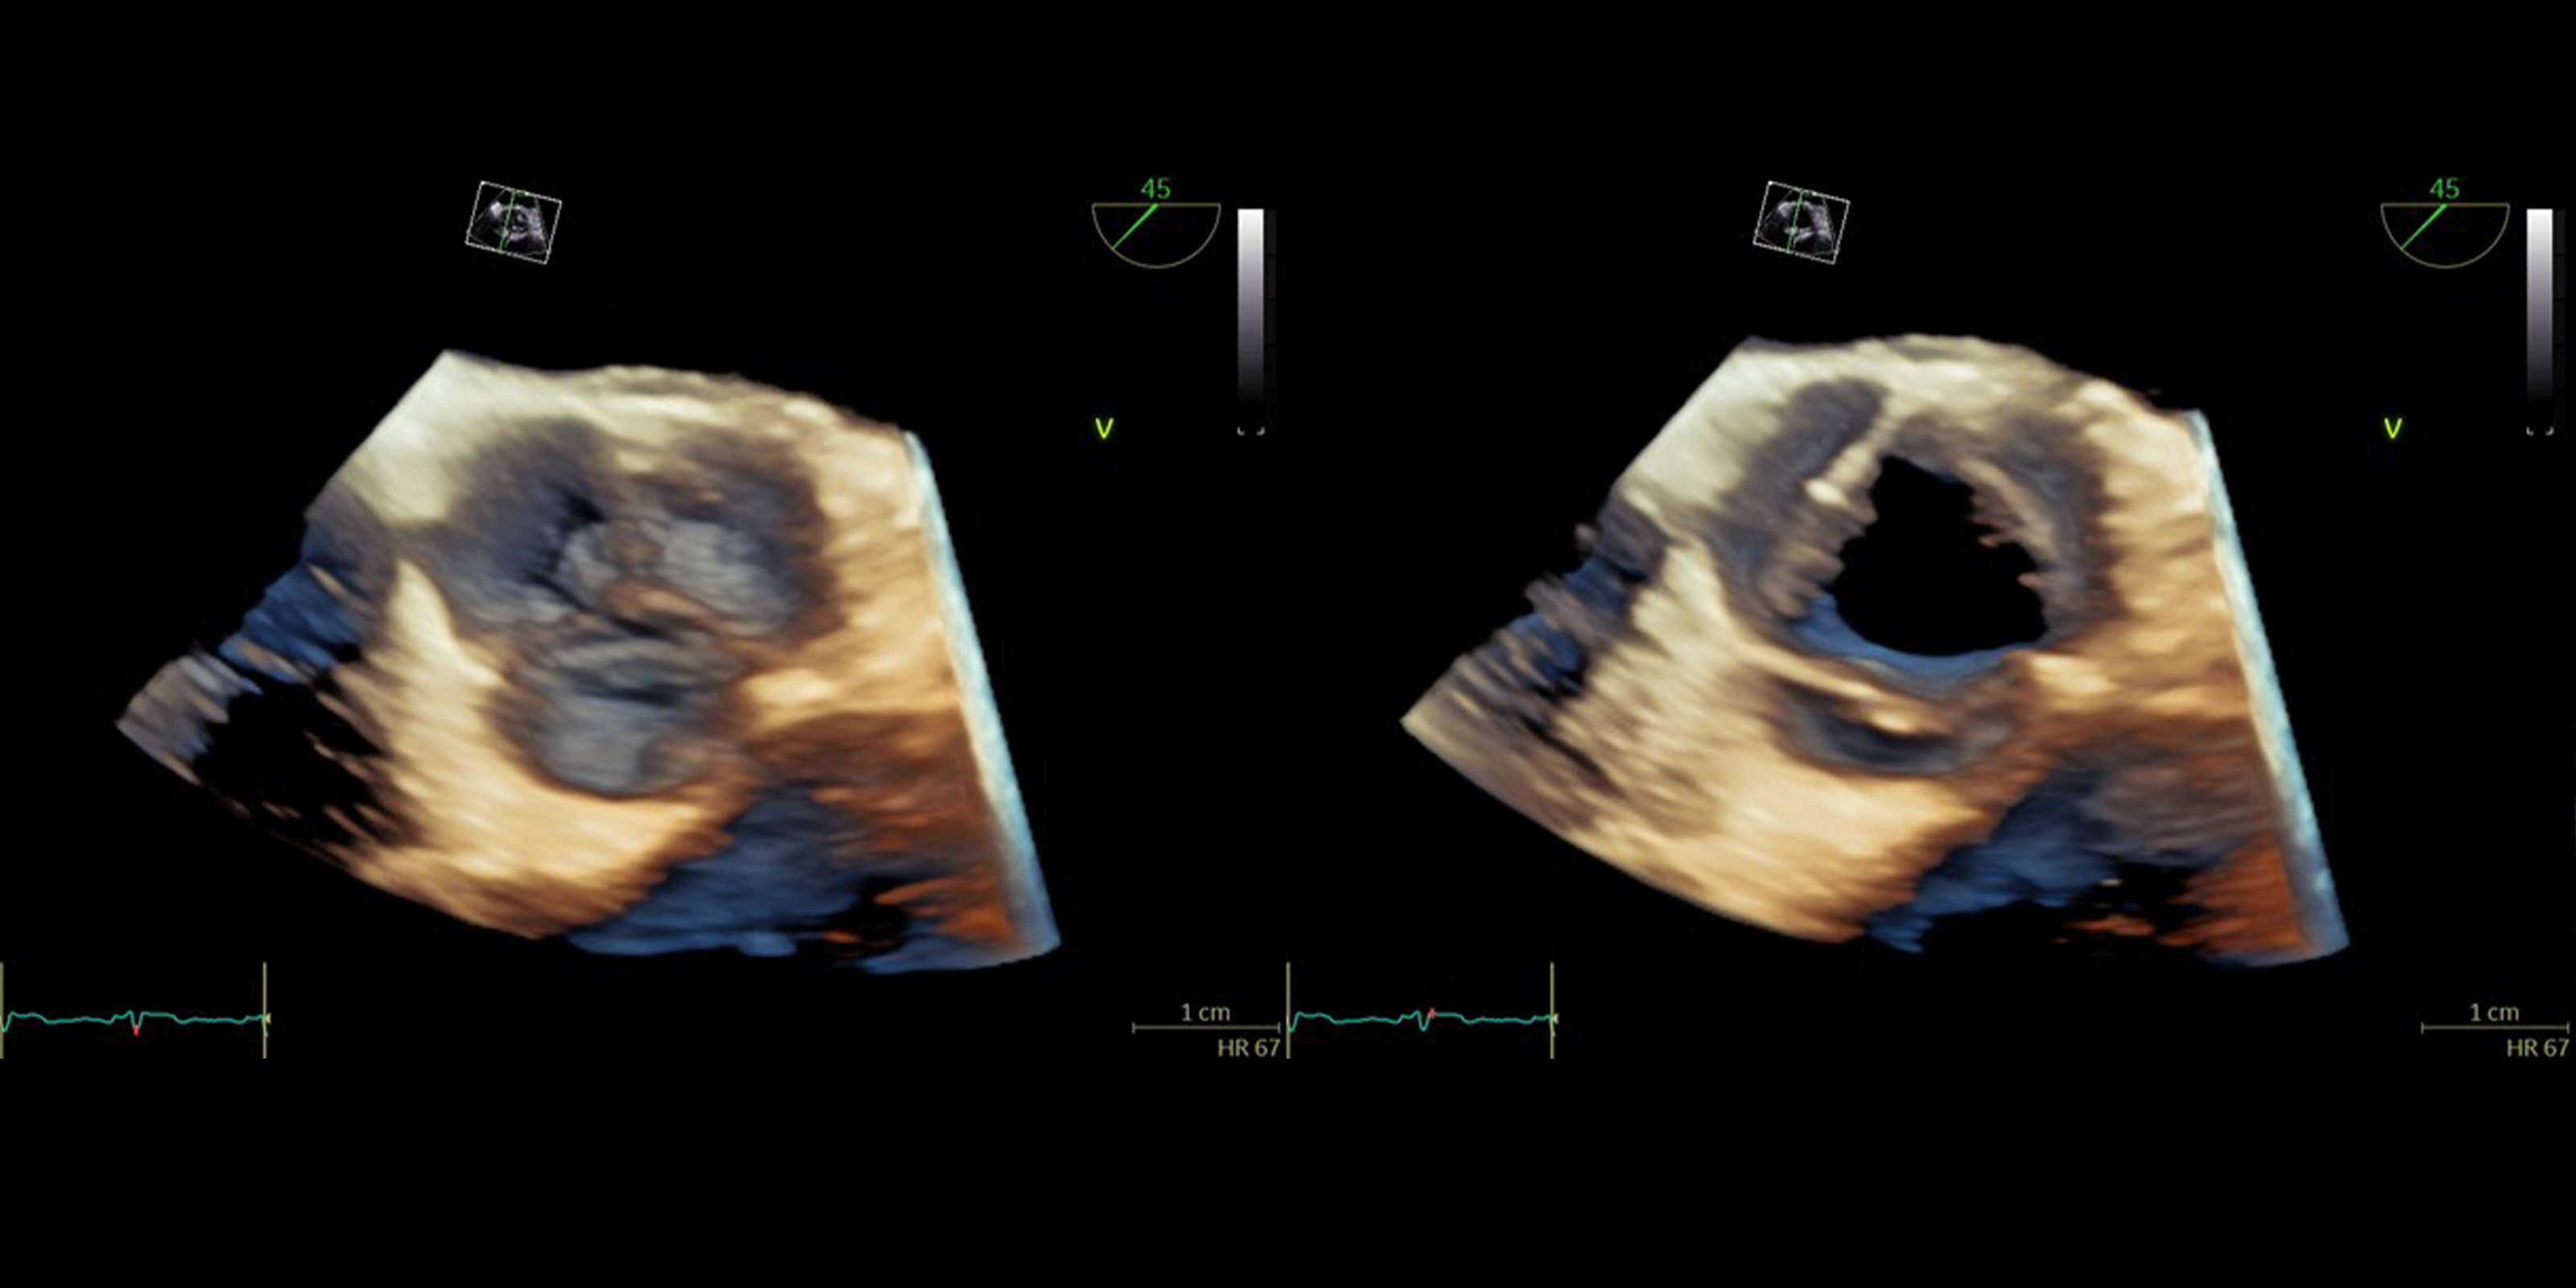

新たな診断の世界

UlPath(ウルパス)は「超音波を学びたい人」に開かれた、オンライン学習プラットフォームです。超音波技術の基礎から専門的な応用まで、段階的な学習プロセスに応じたコンテンツや、超音波医学の専門家として必要な知識・技能の習得を目指すためのコンテンツなど広く収載していきます。